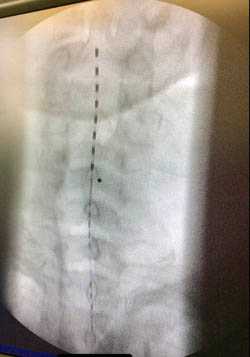

Для ЧЭССМ применялся аппарат БиоСтим-5 (ООО «Косима»). Электроды (WFB02 QWER, Китай; BF4, LEAD-LOC, Inc., США) с адгезивным токопроводящим слоем фиксировали накожно. Стимулирующий электрод (катод) в виде диска диаметром 2,5 см располагали на средней линии позвоночника между остистыми отростками на 3 уровнях: С5—6, Th11—12 и L1—2. Индифферентные электроды (аноды) помещали симметрично над гребнями подвздошных костей. Стимуляция осуществлялась прямоугольными импульсами (монополярными и/или биполярными) длительностью 1 мс, заполненными несущей частотой 10 кГц. Величину тока подбирали индивидуально, чтобы он не был болезненным и в то же время вызывал сокращение мышц нижних конечностей. Диапазон амплитуды использованных токов составлял 30—120 мА. В течение процедуры величину тока постепенно увеличивали на 20—40 мА. Частота импульсов составляла 15—30 Гц. ЧЭССМ проводили одновременно с двигательной тренировкой на тренажере для активно-пассивной реабилитации верхних и нижних конечностей (Thera vital, «Medica Medizintechnik», Германия). Режим тренировки подбирали индивидуально в зависимости от функциональных способностей больных и поставленных реабилитационных задач. Также для улучшения статики использовали упражнения сидя на стуле, стоя в коленоупоре с постепенным уменьшением площади опоры. При выборе параметров стимулирующих воздействий ориентировались на результаты использования ЧЭССМ для регуляции локомоторных [8] и постуральных функций [10] у пациентов с вертебро-спинальной патологией.

В зависимости от возраста пациента и уровня расположения стимулирующих электродов подбираются оптимальные параметры силы тока. Каждый из каналов стимулятора выдаёт импульсы тока в диапазоне от 0 до 300 мА с шагом 1 мА. Электроды (катод) фиксируются между остистыми отростками позвонков в зависимости от уровня повреждения спинного мозга, индифферентный электрод (анод) располагается над гребнями подвздошных костей. Средний ток, выдаваемый стимулятором по каждому каналу (постоянная составляющая тока) равен нулю. Это обеспечивает нулевой потенциал на коже в месте приложения электродов, что предотвращает возможный ожог кожи в случае большой амплитуды импульсов. В результате проведённого анализа были определены предельно допустимые величины силы, рекомендуемые для проведения ЧЭССМ в различных возрастных группах. Предельно допустимая сила тока для проведения ЧЭССМ у детей с позвоночно-спинномозговой травмой в возрасте до 7 лет составляет 40мА, от 7 до 12 лет - 80мА, старше 12 лет - 150мА.

При повреждении спинного мозга на уровне шейного утолщения и грудных сегментов показано проведение ЧЭССМ на двух уровнях - в зоне повреждения и на уровне поясничного утолщения; при повреждении спинного мозга на уровне поясничного утолщения показано проведение ЧЭССМ на одном уровне (поясничное утолщение).